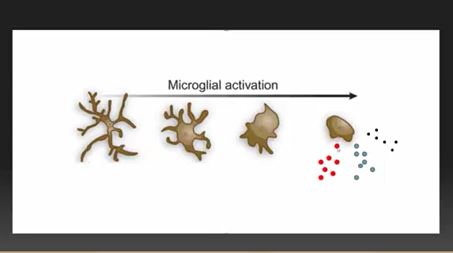

The study authors proposed that microglial cell activation was causing the severe fatigue found in multiple sclerosis

This was kind of a hybrid hypothesis-driven exploratory study. Since all we know for sure, regarding the fatigue in MS, is that it’s not coming from the nerve lesions – the study needed to be exploratory. The study authors, though, had a hunch: microglial activation and the neuroinflammation it was causing was producing the fatigue. That idea, of course, fits right with similar speculations regarding ME/CFS/FM.

Because the site of the neuroinflammation was unclear, Medical Express reported that the researchers used what they called a “snooper” – a PET scan which used a radiolabeled “detective” or tracer ([F-18]PBR06 radioligand) to bind to activated microglial cells. This was the first time microglial activation was assessed with regard to fatigue in MS. Not knowing where to look, they looked everywhere – and their finding, from an ME/CFS perspective, anyway – was astounding.

- Proposing that microglial activation and neuroinflammation might be causing the fatigue M.S. researchers did an amall open-ended PET scan of the brain

- The authors proposed that a microglial activation in the basal ganglia could be producing fatigue in a number of diseases including ME/CFS and urged more studies be done.

Another unifying hypothesis – this time for fatigue and possibly even for neurological disorders – microglial activation and neuroinflammation

Fatigue is one of the most common and disabling symptoms of MS, yet it is not, oddly enough, related to the lesions which cause the movement and other problems in the disease. Some studies have found brain abnormalities that are associated with fatigue in MS, but it’s never been clear what’s causing them. A small exploratory MS study may have provided an answer – microglial activation and neuroinflammation.

These studies suggest that microglial activation could be contributing to reduced basal ganglia activation and fatigue not just in ME/CFS and FM, but in MS and other diseases.

Some researchers – including these MS researchers – believe that microglial activation lights the fire that produces central nervous system diseases like MS, as well as other diseases like Parkinson’s disease, ME/CFS, FM and GWI. The type of disease that is produced depends on the where and how of the neuroinflammation and the environment; i.e. the biological construct of the individual involved.